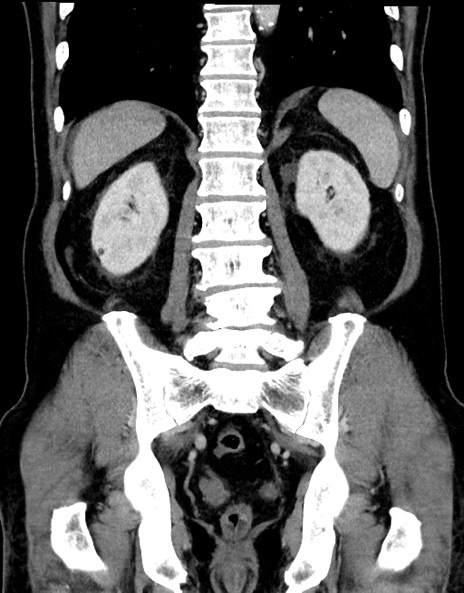

症例15(冠状断像)

【症例】70歳代男性

【主訴】腹痛

【現病歴】今朝から腹痛あり。全体的に痛い。特に左上の方。排ガスが今日はない。冷や汗が出る。

【既往歴】直腸癌術後

【身体所見】左側腹部〜上腹部に圧痛あり。腹膜刺激症状明らかなではない。軽度反跳痛。左下腹部に術後瘢痕あり。

【データ】WBC 7700、CRP 0.02